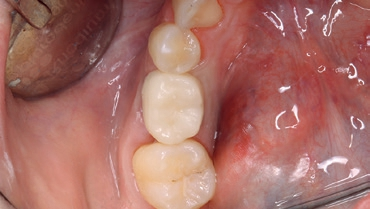

Nach einer Einheilzeit von 3 Monaten wurde die Osseointegration röntgenologisch kontrolliert, das Provisorium über ein okklusales Re-Opening entfernt und anschließend die Implatatposition mit dem Intraoralscanner CEREC Primescan von Dentsply Sirona und der CEREC SW 5 erneut gescannt.

Dabei nutzte ich das durch die provisorische Versorgung bereits bestehende Emergenzprofil des Weichgewebes für eine optimale definitive Versorgung. Etwaige okklusale Differenzen während der Einheildauer ließen sich auf diese Weise gut ausgleichen. Die finale Versorgung habe ich 2-teilig ausgeführt. Die Unterkonstruktion wurde mittels eines individuellen Zirkonabutments aus inCoris Meso Block gefräst und anschließend gesintert (CEREC SpeedFire). Die Krone wurde aus einem Celtra Duo LT Block geschliffen und im Anschluss individuell bemalt und glasiert (Abb. 18 bis 22).